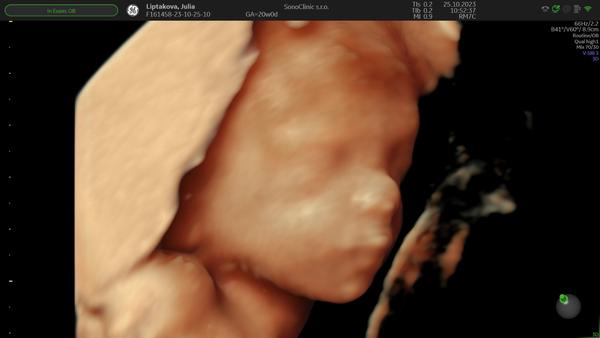

@lechmanova super, tesim sa s tebou, ze vsetko v poriadku. Aj ti urobili nejake pekne foto 3D tvaricky? Tiez by som na genetiku nesla..

@jujulip jej, ten je krasny..uzasna fotka..tesim sa aj s tebou...uz som na rade len ja buduci piatok..

@lechmanova to som dostala na usb, aj videa ako sa malý smeje a cmula si palec 🙈 a potom už len organy..

@jujulip váš malý cmúlal palček a náš počítal palce po jednom si ich vyrovnával 😁 zlaté to bolo